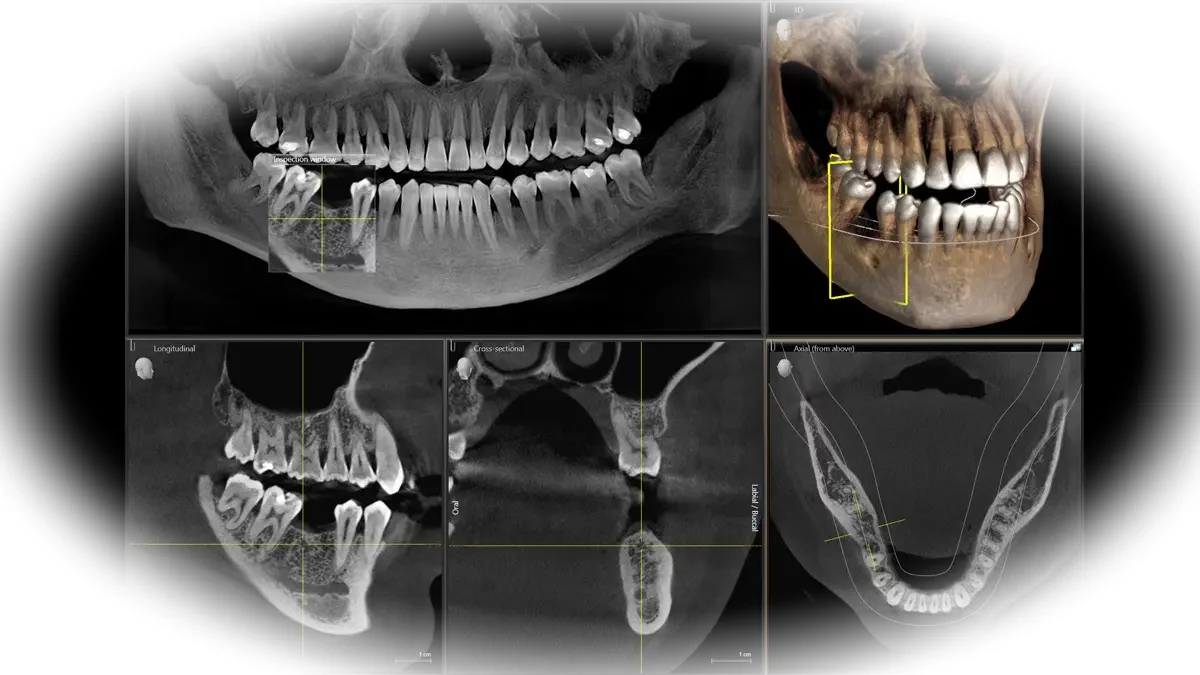

Главная особенность томографа заключается в том, что он может выполнять серию снимков, на основании которых формируется 3D модель объектов исследования. Изображения, полученные методом 3D-томографии, очень точные, и стоматолог может изучать их в различных проекциях, добавлять нужные фильтры, чтобы точно визуализировать самые мелкие детали всех анатомических структур челюсти. Специально созданное для такой диагностики программное обеспечение генерирует результат с помощью «искусственного интеллекта» – подбора соответствующего диагноза из базы загруженных изображений.

Снимки, которые получают при использовании методики компьютерной томографии, представляют собой трехмерное изображение челюсти. Добиться такого эффекта можно посредством разных вариантов позиционирования аппарата и системы фиксации на трех точках. 3D можно рассмотреть во всех плоскостях без искажений и малейших погрешностей, а главное – получить точную картину состояния зубочелюстной системы.